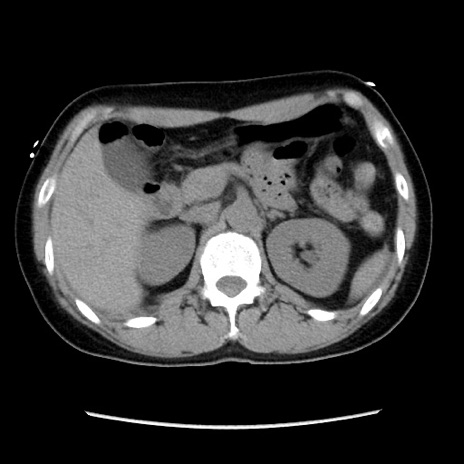

症例10(横断像)

【症例】 50歳代女性

【主訴】 腹痛

【現病歴】前日生レバーを食べた。今朝に排便あり。 昼前に突然発症の腹痛を生じ、当院救急外来を受診した。

【既往歴】 子宮筋腫にてで子宮全摘後

【身体所見】 意識清明、腹部:平坦、軟、下腹部やや左を中心に圧痛・反跳痛あり、筋性防御あり

【データ】WBC 7800、CRP 0.07